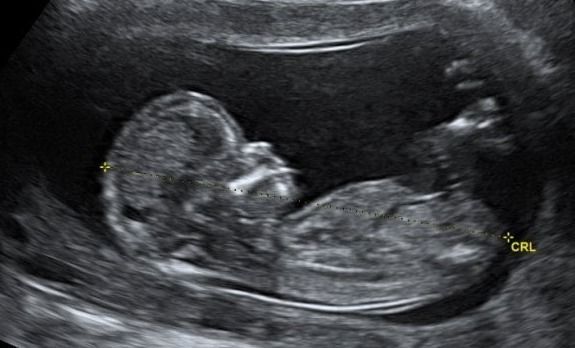

Contamos con gran variedad de estudios como abdomen, pélvico, tiroides, obstétrico 3D y 4D, protocolos maternofetales, estructural, entre otros.

MATERNO FETAL

PERFIL BIOFÍSICO FETAL